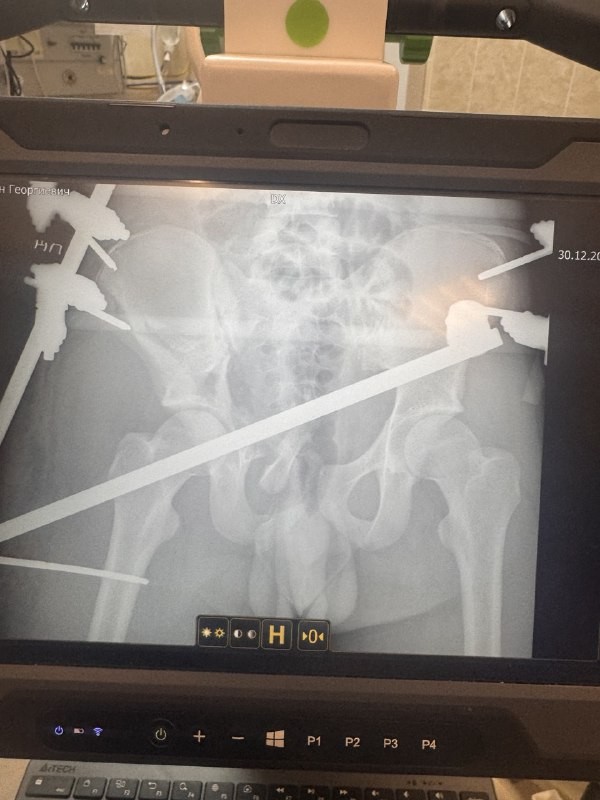

У парня диагностировали многооскольчатый перелом таза, массивную забрюшинную гематому, повреждения внутренних органов и закрытую черепно-мозговую травму. Ситуация осложнялась развивающимся травматическим шоком.

Для остеосинтеза был использован современный рентгеннегативный аппарат внешней фиксации, позволяющий с высокой точностью сопоставить осколки.